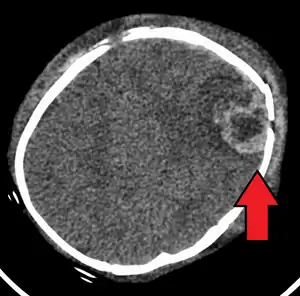

![]() | |

| An intraparenchymal bleed with overlying skull fracture from shaken baby syndrome | |